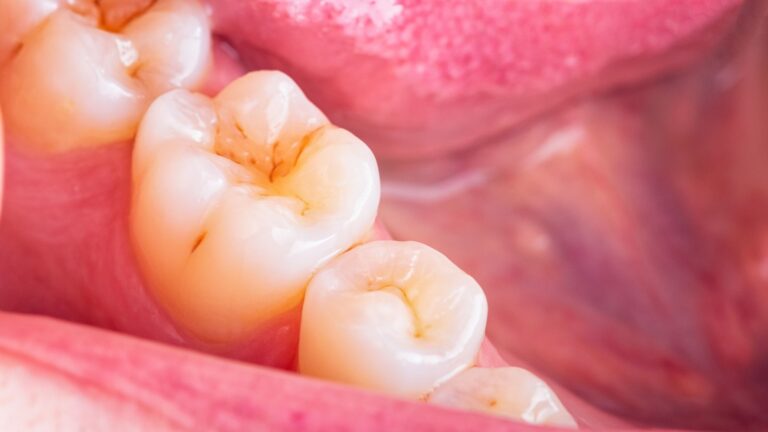

Czym jest elektrokoagulacja? Elektrokoagulacja to zabieg polegający na kontrolowanym wykorzystaniu prądu elektrycznego w celu zamknięcia naczyń krwionośnych oraz usunięcia zmienionych tkanek. W stomatologii metoda ta znajduje zastosowanie przede wszystkim w chirurgii i periodontologii. Stomatolog w nowoczesnej klinika stomatologiczna Kraków wykorzystuje…